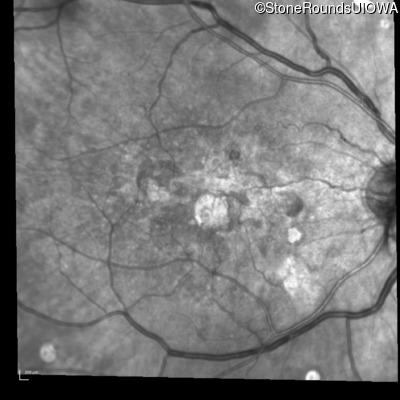

Visit at age: 60 years (Visit 3)

Infrared Fundus Photograph - Right - 20/150

Exemplar